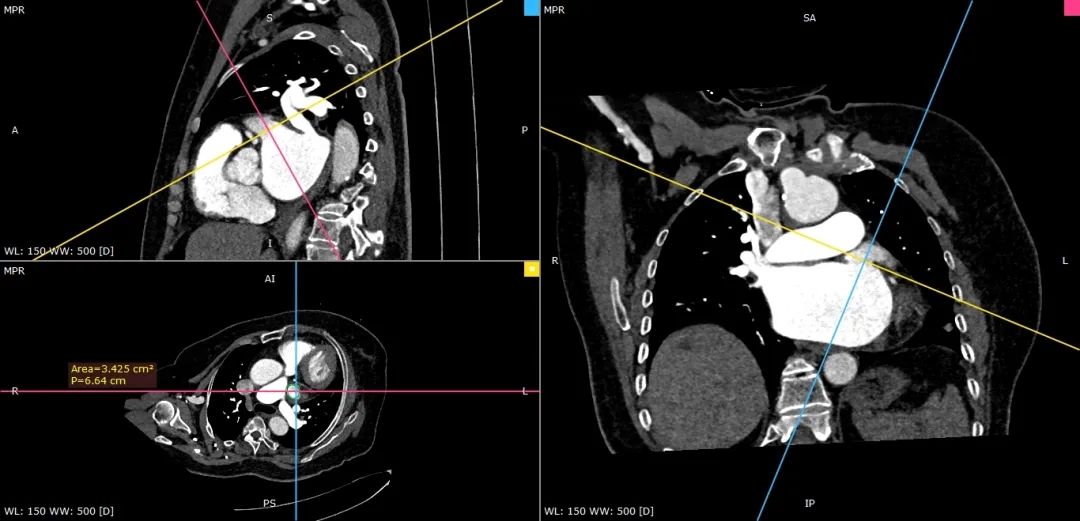

术前CTA确认心耳形态及位置

低位双分叶型左心耳

术前检查:心脏CT三维重建确认开口直径与心耳深度

RAO30度

CAU20度

左心耳大小20.1*17mm

RAO0度

CRA20度

左心耳大小20.3*15.5mm

RAO170度

CAU30度

左心耳大小20.2*17mm

CT三维平面左心耳开口形态及大小

左心耳开口近圆形,MPR周长66.4mm,化圆直径21.1mm,预选LAFDQ-23封堵器进行封堵